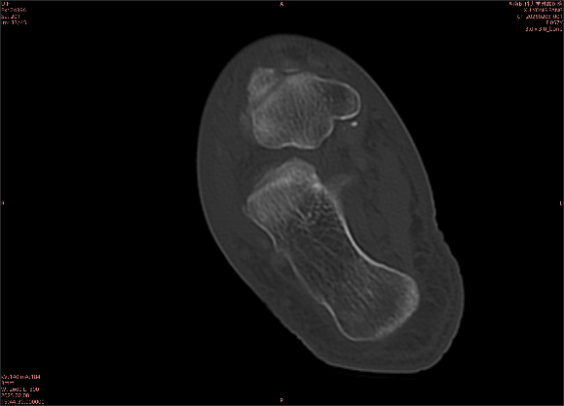

舉例圖像

圖1

專業(yè)解釋看不懂沒關(guān)系,大家看圖1和圖2就可以了,這是同一個(gè)患者跟骨的磁共振和CT圖像,圖1的紅色箭頭指示的黑線就是磁共振圖像顯示的骨折線,一目了然。而對比圖2的CT圖像上并未顯示異常。